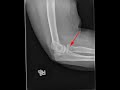

Radial HED fracture

This is a patient who presented to the emergency room with elbow pain. Radiographs of elbow were obtained. The frontal radiograph does not demonstrate any siginficant abnormality. However, on the lateral radiograph as indicated by the red arrow, there is a nondisplaced fracture of the radial head with intrarticular extension into the elbow joint. As with all intrarticular fractures, there is a moderate to large elbow joint effusion as indicated by a posterior fat pad sign as well as elevation of the anterior fat pad. Radial head fractures are the most common type of elbow fractures in adults. Nondisplaced fractures are treated by casting. Displaced fractures or radial head fractures associated with elbow dislocation may be treated surgically.